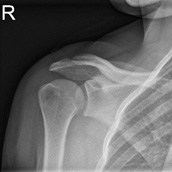

Plain Films: Three different views of the shoulder are typically used to evaluate shoulder pathology: anterior-posterior view (Grashey view), axillary lateral view, and the outlet view. In the setting of SLAP tears, plain films are helping for assessing for any other shoulder pathology thay may be present.

Image 6 [9]. AP view of the shoulder (“Grashey” view).